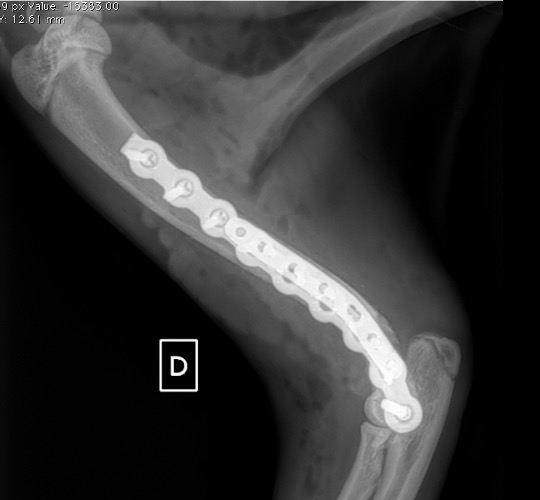

Exemple 1 :

Figure 1 : Pré-op

Figure 2 : Post-Op Immédiat

Figure 3 : Post-Op 1 Mois

Figure 3 : Post-Op 2 Mois

Notre préférence va vers le placement de deux plaques humérales : une médiale de la plus grande taille possible et l’autre latérale, généralement d’une taille inférieure à la première. Dans l’exemple 1 (chat européen), une plaque de 2 mm est utilisée médialement et une plaque de 1,5 mm latéralement. Dans l’exemple 2 (chien Malinois), une plaque de 3,5 mm est utilisée médialement et une plaque de 2,7 mm latéralement.